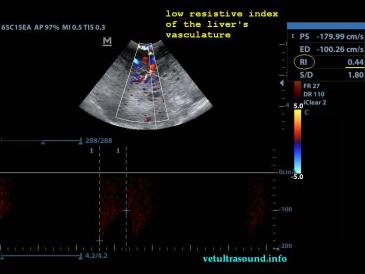

Στον υπέρηχο βρέθηκε ανομοιογένεια του ηπατικού παρεγχύματος, πολυάριθμοι κυστικοί σχηματισμοί οι οποίοι καταλάμβαναν κυρίως τον δεξιό πλάγιο λοβό του οργάνου(pic1&2). Η ροή του αίματος στη πυλαία φλέβα με τη βοήθεια του Pulse Wave Doppler βρέθηκε φυσιολογική(pic3), ενώ σε κλάδο της δεξιάς ηπατικής αρτηρίας ο δείκτης αγγειακής αντίστασης βρέθηκε μειωμένος(normal RI≈ 0.55)(pic4). Στοιχείο που μας δείχνει πως είτε η αγγείωση στη συγκεκριμένη περιοχή είναι νεόπλαστη, είτε λόγω χρόνιας νόσου ο διάμεσος ιστός που περιβάλλει τα αγγεία έχει χάσει την σκληρότητά του. Μικρή ποσότητα ασκιτικού υγρού βρέθηκε ανάμεσα στις εντερικές έλικες. Χωρίς παθολογικά διογκωμένους λεμφαδένες εκτιμήθηκε η κοιλιακή κοιλότητα(pic5). Οι υπόλοιπες δομές ελέγχθηκαν χωρίς παθολογικά ευρήματα.